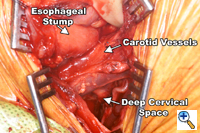

A generous low collar incision is performed and subplatysmal flaps are raised inferiorly and superiorly. The strap muscles and the medial heads of the sternocleidomastoid are divided. The esophagus (previously fully mobilized from the thorax) is retrieved from the prevertebral space. The esophagus is divided distally and the specimen is retrieved in the abdomen. The previously dissected recurrent nerves are easy to visualize (especially the right recurrent) and any residual nodal tissue is excised (Figure 6). Next, the nodes posterior and lateral to the carotid sheath are removed along with the supraclavicular nodes (Figure 7). The dissection is limited superiorly by the inferior belly of the omohyoid. Within the abdomen the gastric tube is prepared and the specimen is removed (Figure 8). Gastrointestinal continuity is restored by a cervical esophagogastrostomy.